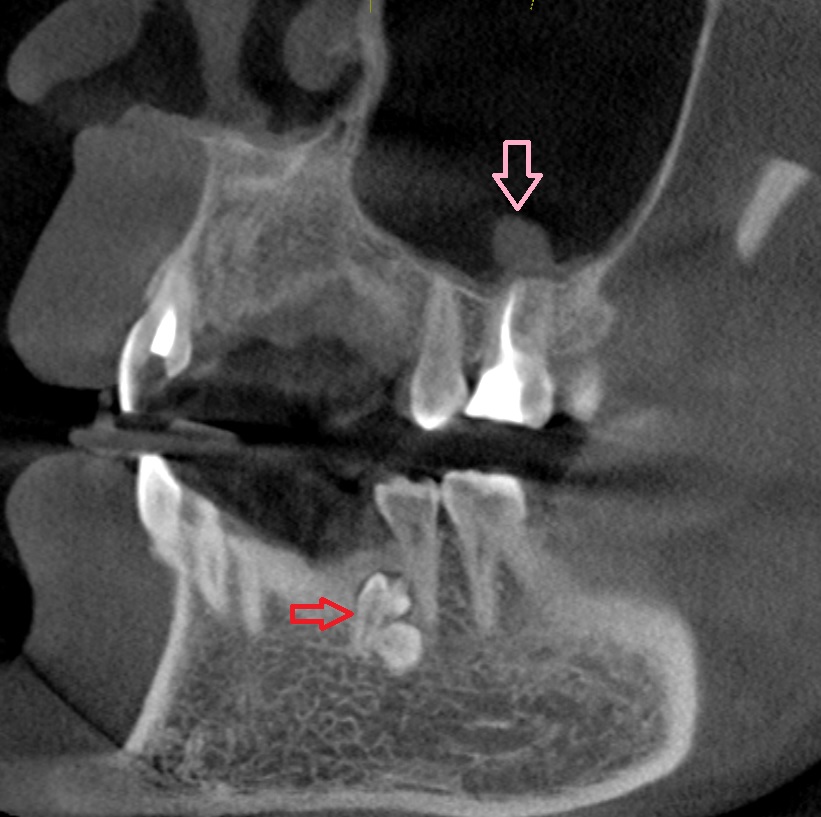

Одонтома нижней челюсти: фотографии и медицинская информация

Раздел: Фотобанк решений